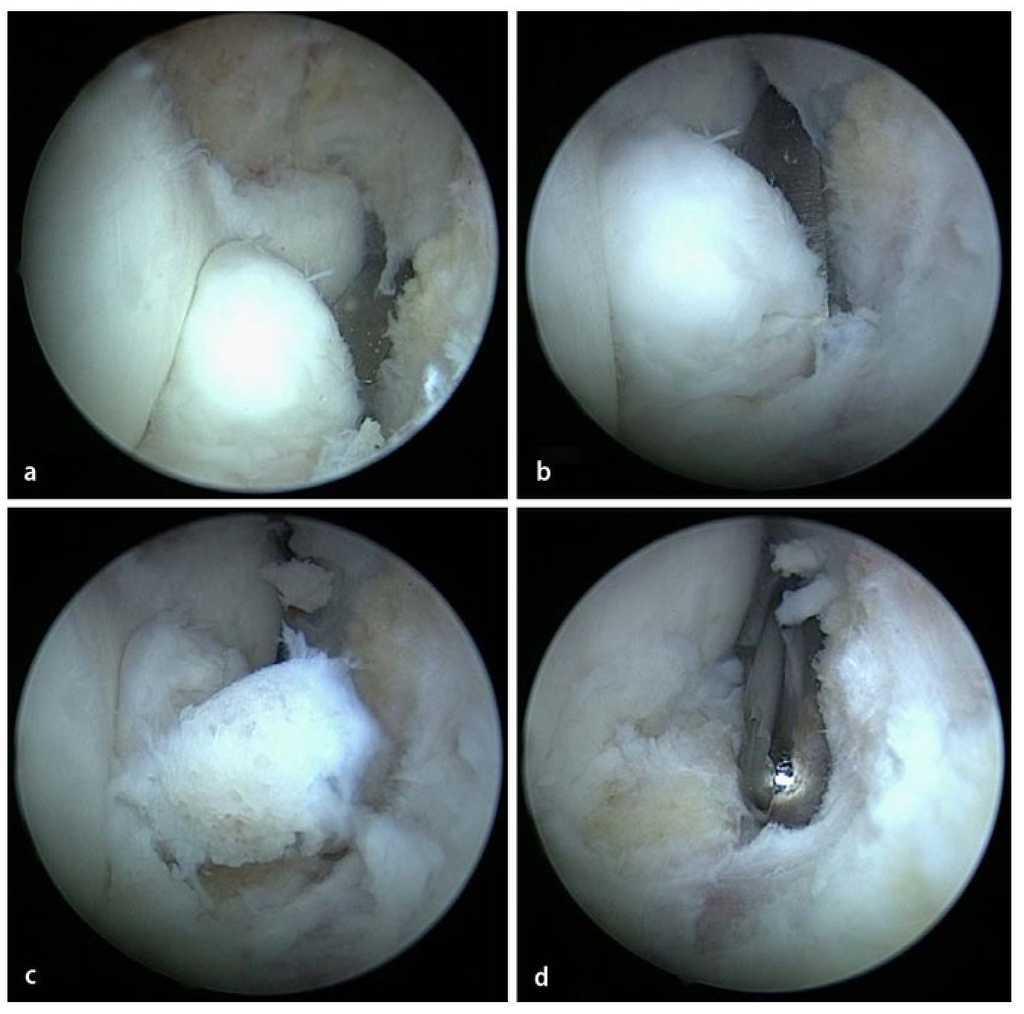

Fig. 10 Después de la sinovialectomía se extraen los cuerpos articulares libres. Según el tamaño de estos cuerpos, la extracción se realizará mediante pinzas o un resector sinovial.

Fig. 11 a, b) Los osteofitos en la zona del proceso coronario se extraen con un cincel Lambotte. c) Los fragmentos osteocondriales se extraen de la articulación con una pinza de agarre. d) El proceso coronoides remanente se alisa con el resector sinovial o una fresa de bola (no representado en la imagen).